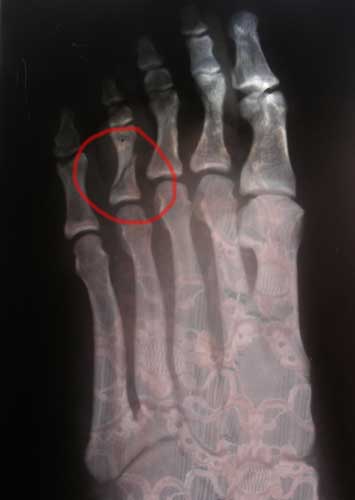

Да, действительно, за пять дней до отъезда на турнир я сломал палец правой ноги как говорится «на ровном месте». На обычной утренней тренировке во время одного из упражнений я случайно споткнулся о ногу Миши Перельмана. Итогом вроде бы безобидного столкновения явилась нелепая и болезненная травма. В травмпункте сделали снимок (он кстати прилагается), наложили гипс и вообще запретили, не то чтобы выступать, а даже наступать на эту ногу. Но я настолько серьёзно готовился к этому турниру (почти три месяца), что находился в очень хорошей форме и из- за такой обидной травмы не участвовать в Чемпионате АКР просто не мог себе позволить.